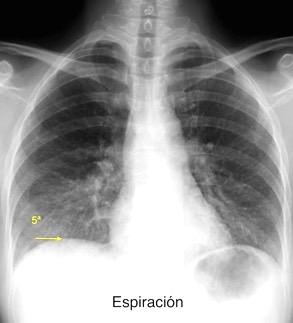

52. PARÁLISIS FRÉNICA

Parálisis frénica

1. Ca. de pulmón

2. Tumor mediastínico maligno. P. ej.: timoma

3. Ganglios mediastínicos

4. Tuberculosis

5. Iatrogénica (post-cirugía cardiaca)

6. Idiopática

MAbbey-Mensah,GN et al. Diaphragm Appearance: A Clue to the Diagnosis of Pulmonary and Extrapulmonary Pathology. Current Problems in Diagnostic Radiology. 2017